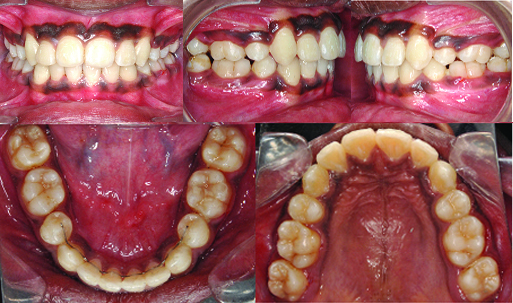

A 13-year-old, male patient presented with a chief complaint of irregularly placed upper front teeth. He was diagnosed as a case of skeletal class I jaw relationship with low mandibular plane angle, class II molar relation on right and class I molar relation on left side, anterior cross bite, crowding of 12mm in upper, 5mm in lower arch. Patient had proclined upper and lower anteriors by 2mm, convex profile and incompetent lips [Table/Fig-1a-c]. The maxillary canines were positioned buccally with significant distal tipping of root. The mandibular arch had moderate crowding with right lateral incisor lingually placed [Table/Fig-2a-e,3a&b].

Pre-treatment Intraoral photographs.